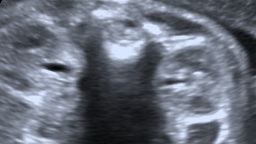

Bilateral hydronephrosis.